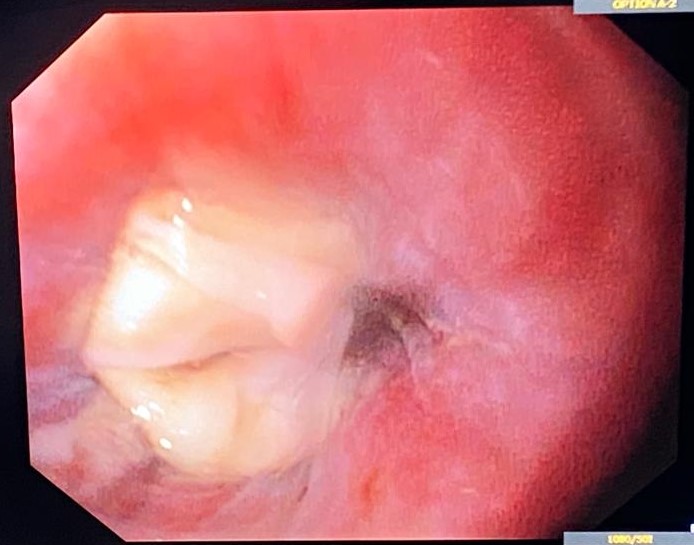

An unexpected esophageal finding: esophagitis dissecans

Diana Ramos1, Rui Morais2, Guilherme Macedo2

1 ULS Castelo Branco; 2 Centro Hospitalar do São João

A 57-year-old male was admitted to the intensive care unit with covid-19 infection, requiring invasive ventilation. Gastroenterology support was requested due to difficulty in placing a nasogastric tube, with a sensation of esophageal obstruction.

Upper endoscopy showed, at the level of the middle esophagus, whitish crepe-paper-like plaques that formed a pseudo-plug. After adequate distension, the lumen was permeable and longitudinal white plaques were adherent to the mucosa and were easily detachable, with the underlying mucosa being hyperemic. Biopsies revealed esophageal mucosa with inflammatory infiltrate, erosion and parakeratosis, confirming a diagnosis of esophagitis dissecans superficialis.

An unexpected esophageal finding: esophagitis dissecans

Fotografia